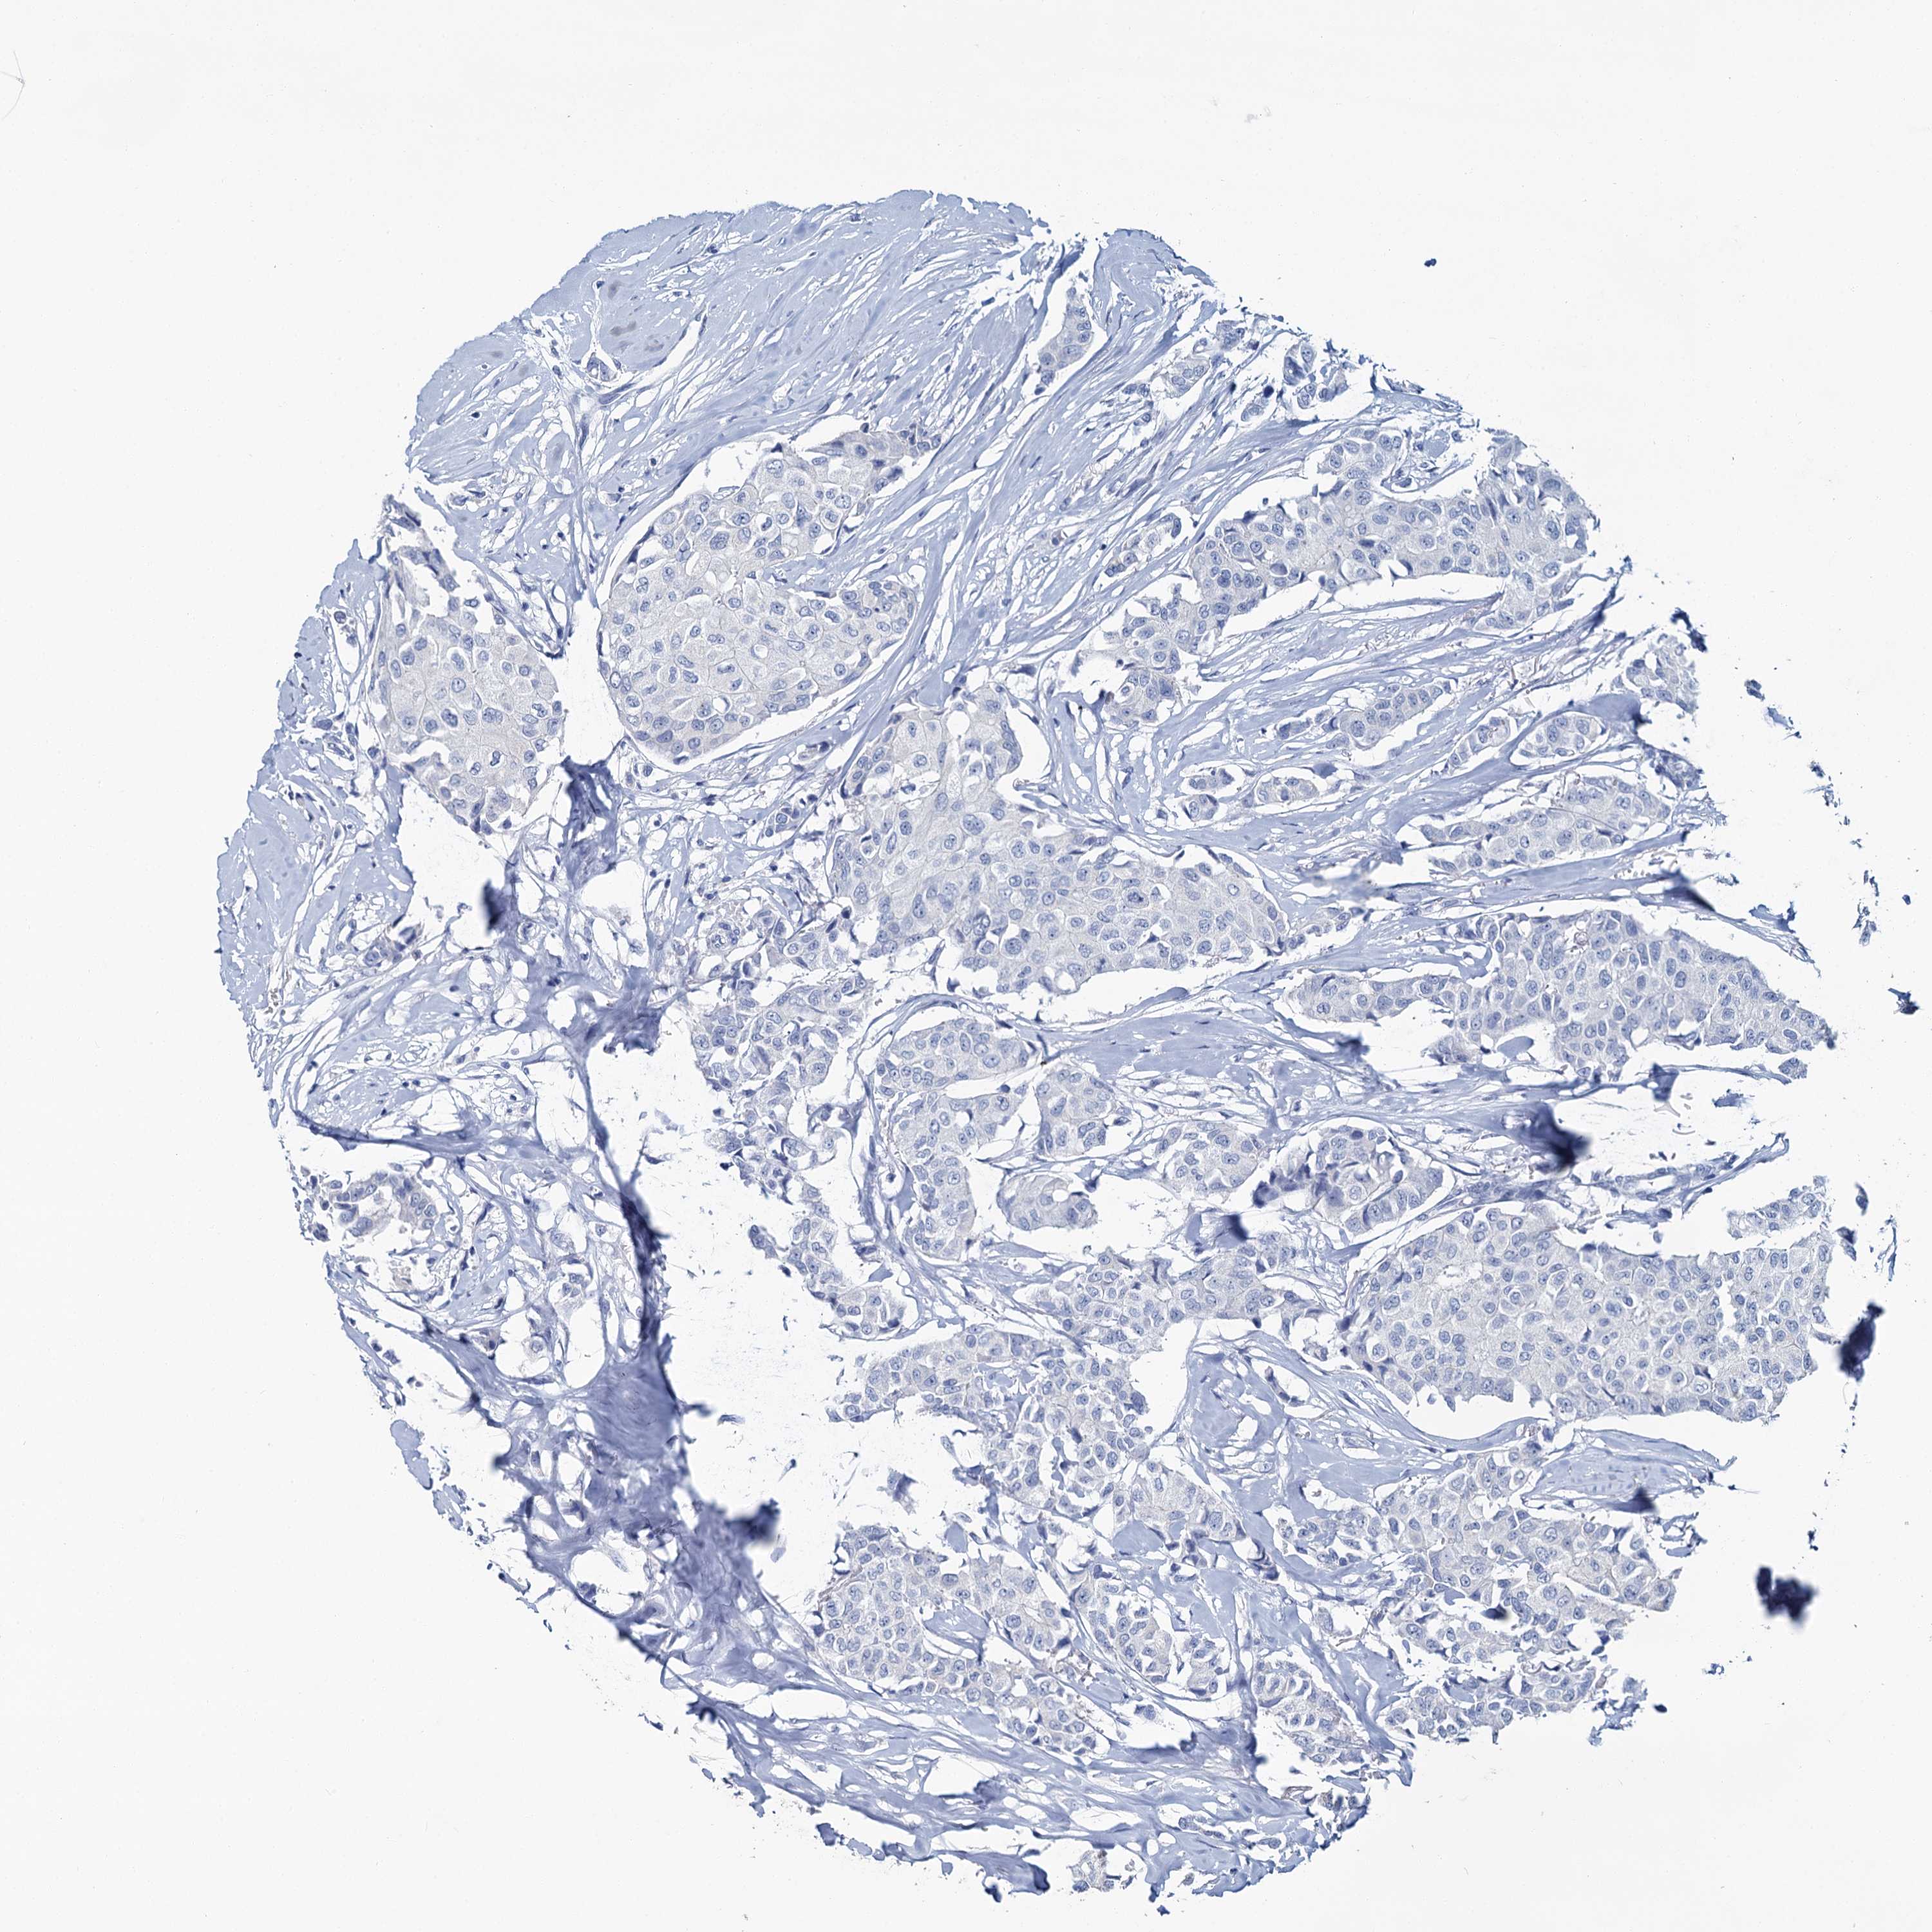

BRCA TCGA BRCA VALIDATION PROTEIN EXPRESSION

ANTIBODIES

AND

VALIDATION